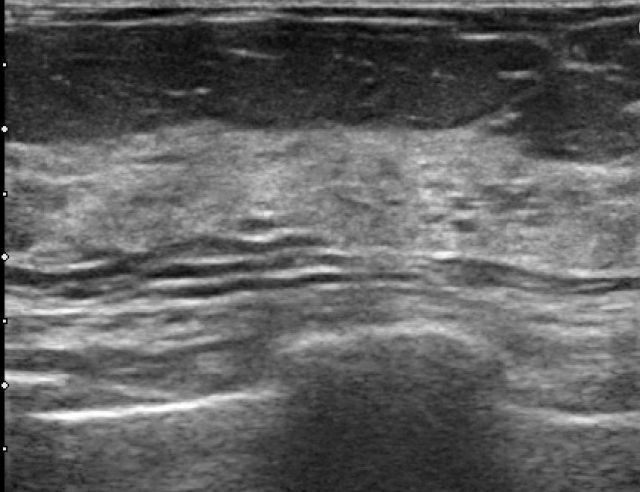

Die Mammasonographie kann als Ultraschalluntersuchung der Brust meist Zysten von anderen Gewebearten unterscheiden. Zysten in der Brust erscheinen als dunkle, runde oder ovale Gebilde mit glatten Rändern und verstärktem Schall hinter der Zyste (sogenannte dorsale Schallverstärkung). Die Größe und Form von Mamma-Zysten kann variieren, je nachdem wie viel Flüssigkeit sie enthalten. Die Flüssigkeit kann klar, milchig oder blutig sein.